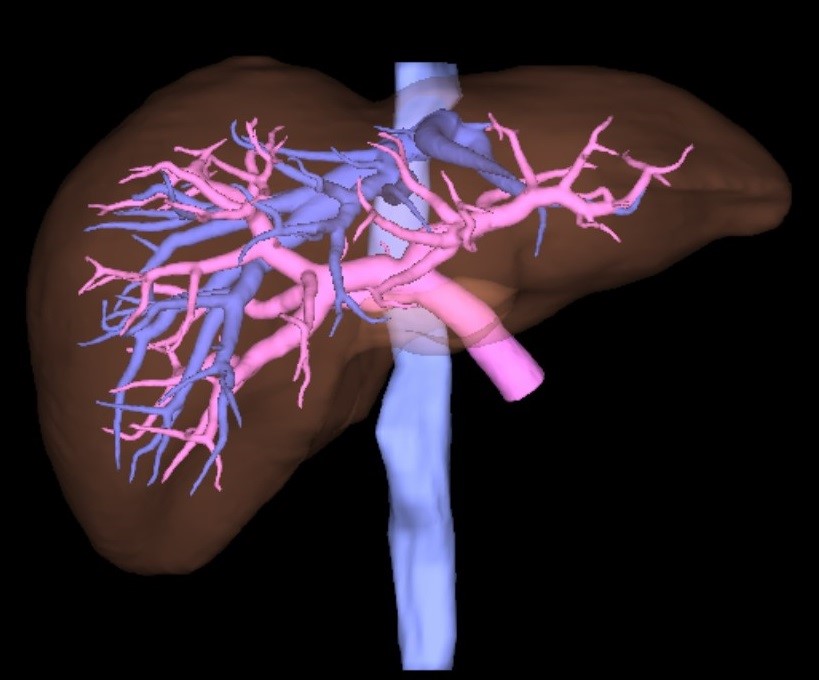

CT検査

当院では、Canon製Aquilion Prime SP 80列を使用しています。短時間で広範囲の撮影ができる他に、撮影したデータを元に任意の角度に合わせた断面像を生成したり、骨や臓器を3次元的に表示して観察することができます。また当院では3D医用画像処理ワークステーション(ZIO・VINCENT)を導入しており、より詳細な3次元画像の作成を行っています。